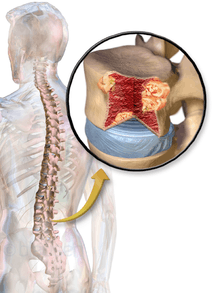

Bone pain

Bone pain affects almost 70% of patients and is the most common symptom.[11] Myeloma bone pain usually involves the spine and ribs, and worsens with activity. Persistent localized pain may indicate a pathological bone fracture. Involvement of the vertebrae may lead to spinal cord compression or kyphosis. Myeloma bone disease is due to the overexpression of receptor activator for nuclear factor κ B ligand (RANKL) by bone marrow stroma. RANKL activates osteoclasts, which resorb bone. The resultant bone lesions are lytic (cause breakdown) in nature and are best seen in plain radiographs, which may show "punched-out" resorptive lesions (including the "raindrop" appearance of the skull on radiography). The breakdown of bone also leads to release of calcium into the blood, leading to hypercalcemia and its associated symptoms.

The work-up of suspected multiple myeloma includes a skeletal survey. This is a series of X-rays of the skull, axial skeleton and proximal long bones. Myeloma activity sometimes appear as "lytic lesions" (with local disappearance of normal bone due to resorption), and on the skull X-ray as "punched-out lesions" (pepper pot skull). Magnetic resonance imaging (MRI) is more sensitive than simple X-ray in the detection of lytic lesions, and may supersede skeletal survey, especially when vertebral disease is suspected. Occasionally a CT scan is performed to measure the size of soft tissue plasmacytomas. Bone scans are typically not of any additional value in the workup of myeloma patients (no new bone formation; lytic lesions not well visualized on bone scan).